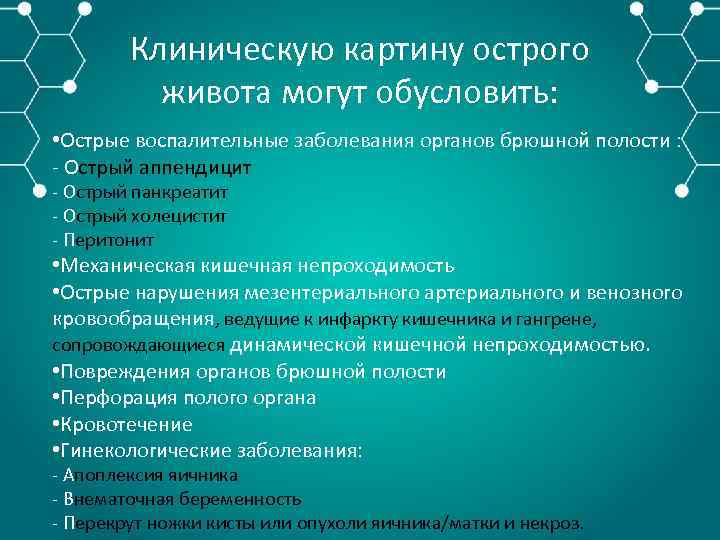

Клиническую картину острого живота могут обусловить: • Острые воспалительные заболевания органов брюшной полости : Острый аппендицит Острый панкреатит Острый холецистит Перитонит • Механическая кишечная непроходимость • Острые нарушения мезентериального артериального и венозного кровообращения, ведущие к инфаркту кишечника и гангрене, сопровождающиеся динамической кишечной непроходимостью. • Повреждения органов брюшной полости • Перфорация полого органа • Кровотечение • Гинекологические заболевания: Апоплексия яичника Внематочная беременность Перекрут ножки кисты или опухоли яичника/матки и некроз.